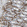

Color-coded cheat-sheet list for 10 cancer types with their key diagnostic (in blue) and prognostic biomarkers (favorable green vs unfavorable red).

| Cancer Type | Biomarkers |

|---|---|

| Breast | CA 15-3, CEA, ER/PR/HER2 status, ER/PR positivity, HER2 overexpression, p53 mutation, high Ki-67 |

| Prostate | PSA, PCA3, Low Gleason score, High PSA, high Gleason score, TMPRSS2-ERG fusion |

| Lung (NSCLC) | CEA, CYFRA 21-1, EGFR mutation, KRAS mutation, TP53 mutation, high N stage |

| Colorectal | CEA, CA 19-9, MSI-high, KRAS/NRAS mutation, BRAF V600E mutation |

| Ovarian | CA-125, HE4, BRCA mutation, High-grade serous histology, p53 mutation |

| Liver (HCC) | AFP, DCP, Early-stage detection, High AFP, vascular invasion, TP53 mutation |

| Pancreatic | CA 19-9, CEA, Early-stage tumor, KRAS mutation, TP53 mutation, SMAD4 loss |

| Gastric | CEA, CA 72-4, HER2 negative, HER2 positive, diffuse type, p53 mutation |

| Melanoma | S-100, LDH, BRAF mutation, High LDH, ulceration, NRAS mutation |

| Bladder | Urine cytology, NMP22, BTA, Low-grade, non-muscle invasive, High-grade, muscle-invasive, TP53 mutation |